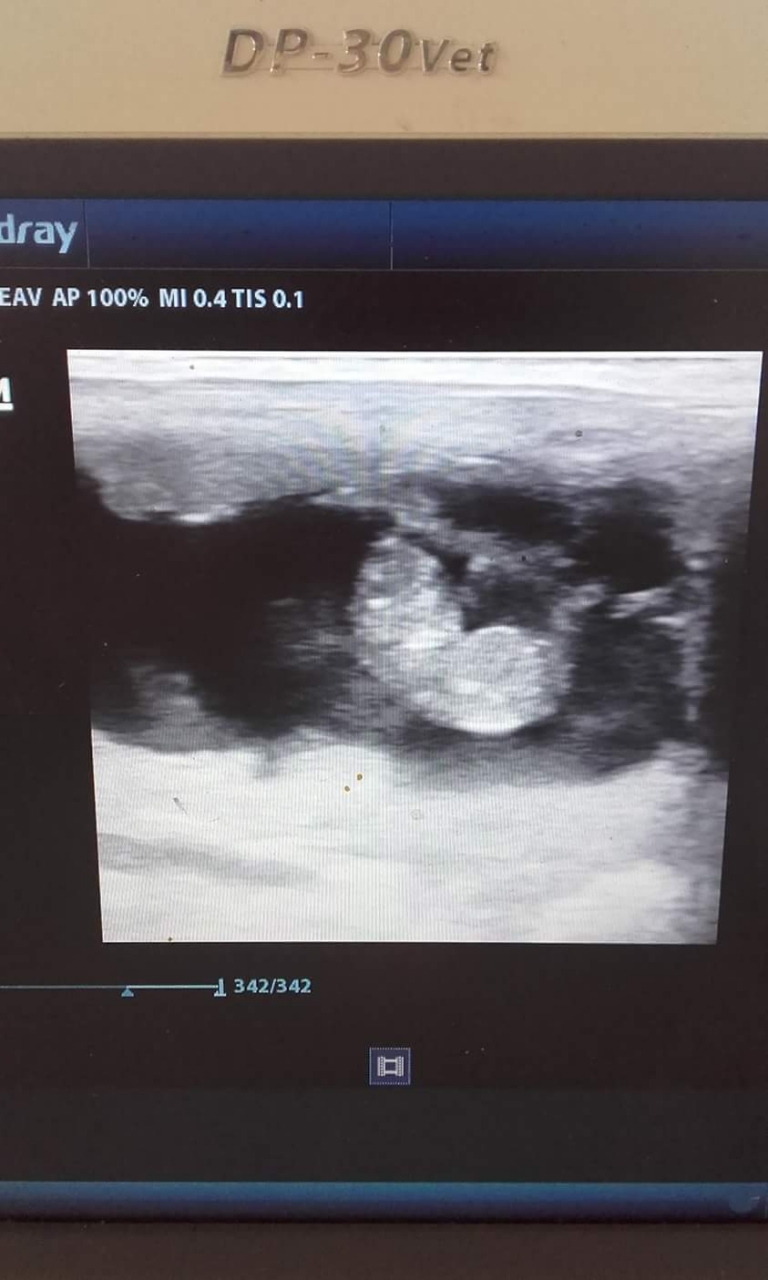

| Dire merci | Hello .... je suis sûre que parmi vous a connu la naissance de symphonie en 2006 et que vous avez suivi pas mal d aventure de ses championnat surtt en 2009 où elle etait championne local , championne regional et vice championne de France des 3 ans HN , elite à 5 ans et j en passe .... je vous annonce que symphonie sera maman pour mai 2018 :-) ![]() |

| Dire merci | eh oui je passe ici faire un coucou car je pense que pas mal sont encore ici et certains je vois sur FB .... eh oui déjà bientôt maman mais seulement juste 1 poulain . j'espère que ce sera une pouliche qui prendra la relève de la maman .... et encore je l'ai mis à l'etalon pour que son membre se repose encore plus longtemps suite d'une blessure à cause d'un DP ... a eu le repos pdt 8 mois après une operation puis a repris 3 concours dont des sans fautes puis difficultés de trouver un petit cavalier . donc je l'ai mis avec un bel étalon champion aussi et reprendra les cso dans 1 ans 1/2 . |

| Dire merci | Symphonie ![]() ![]() |